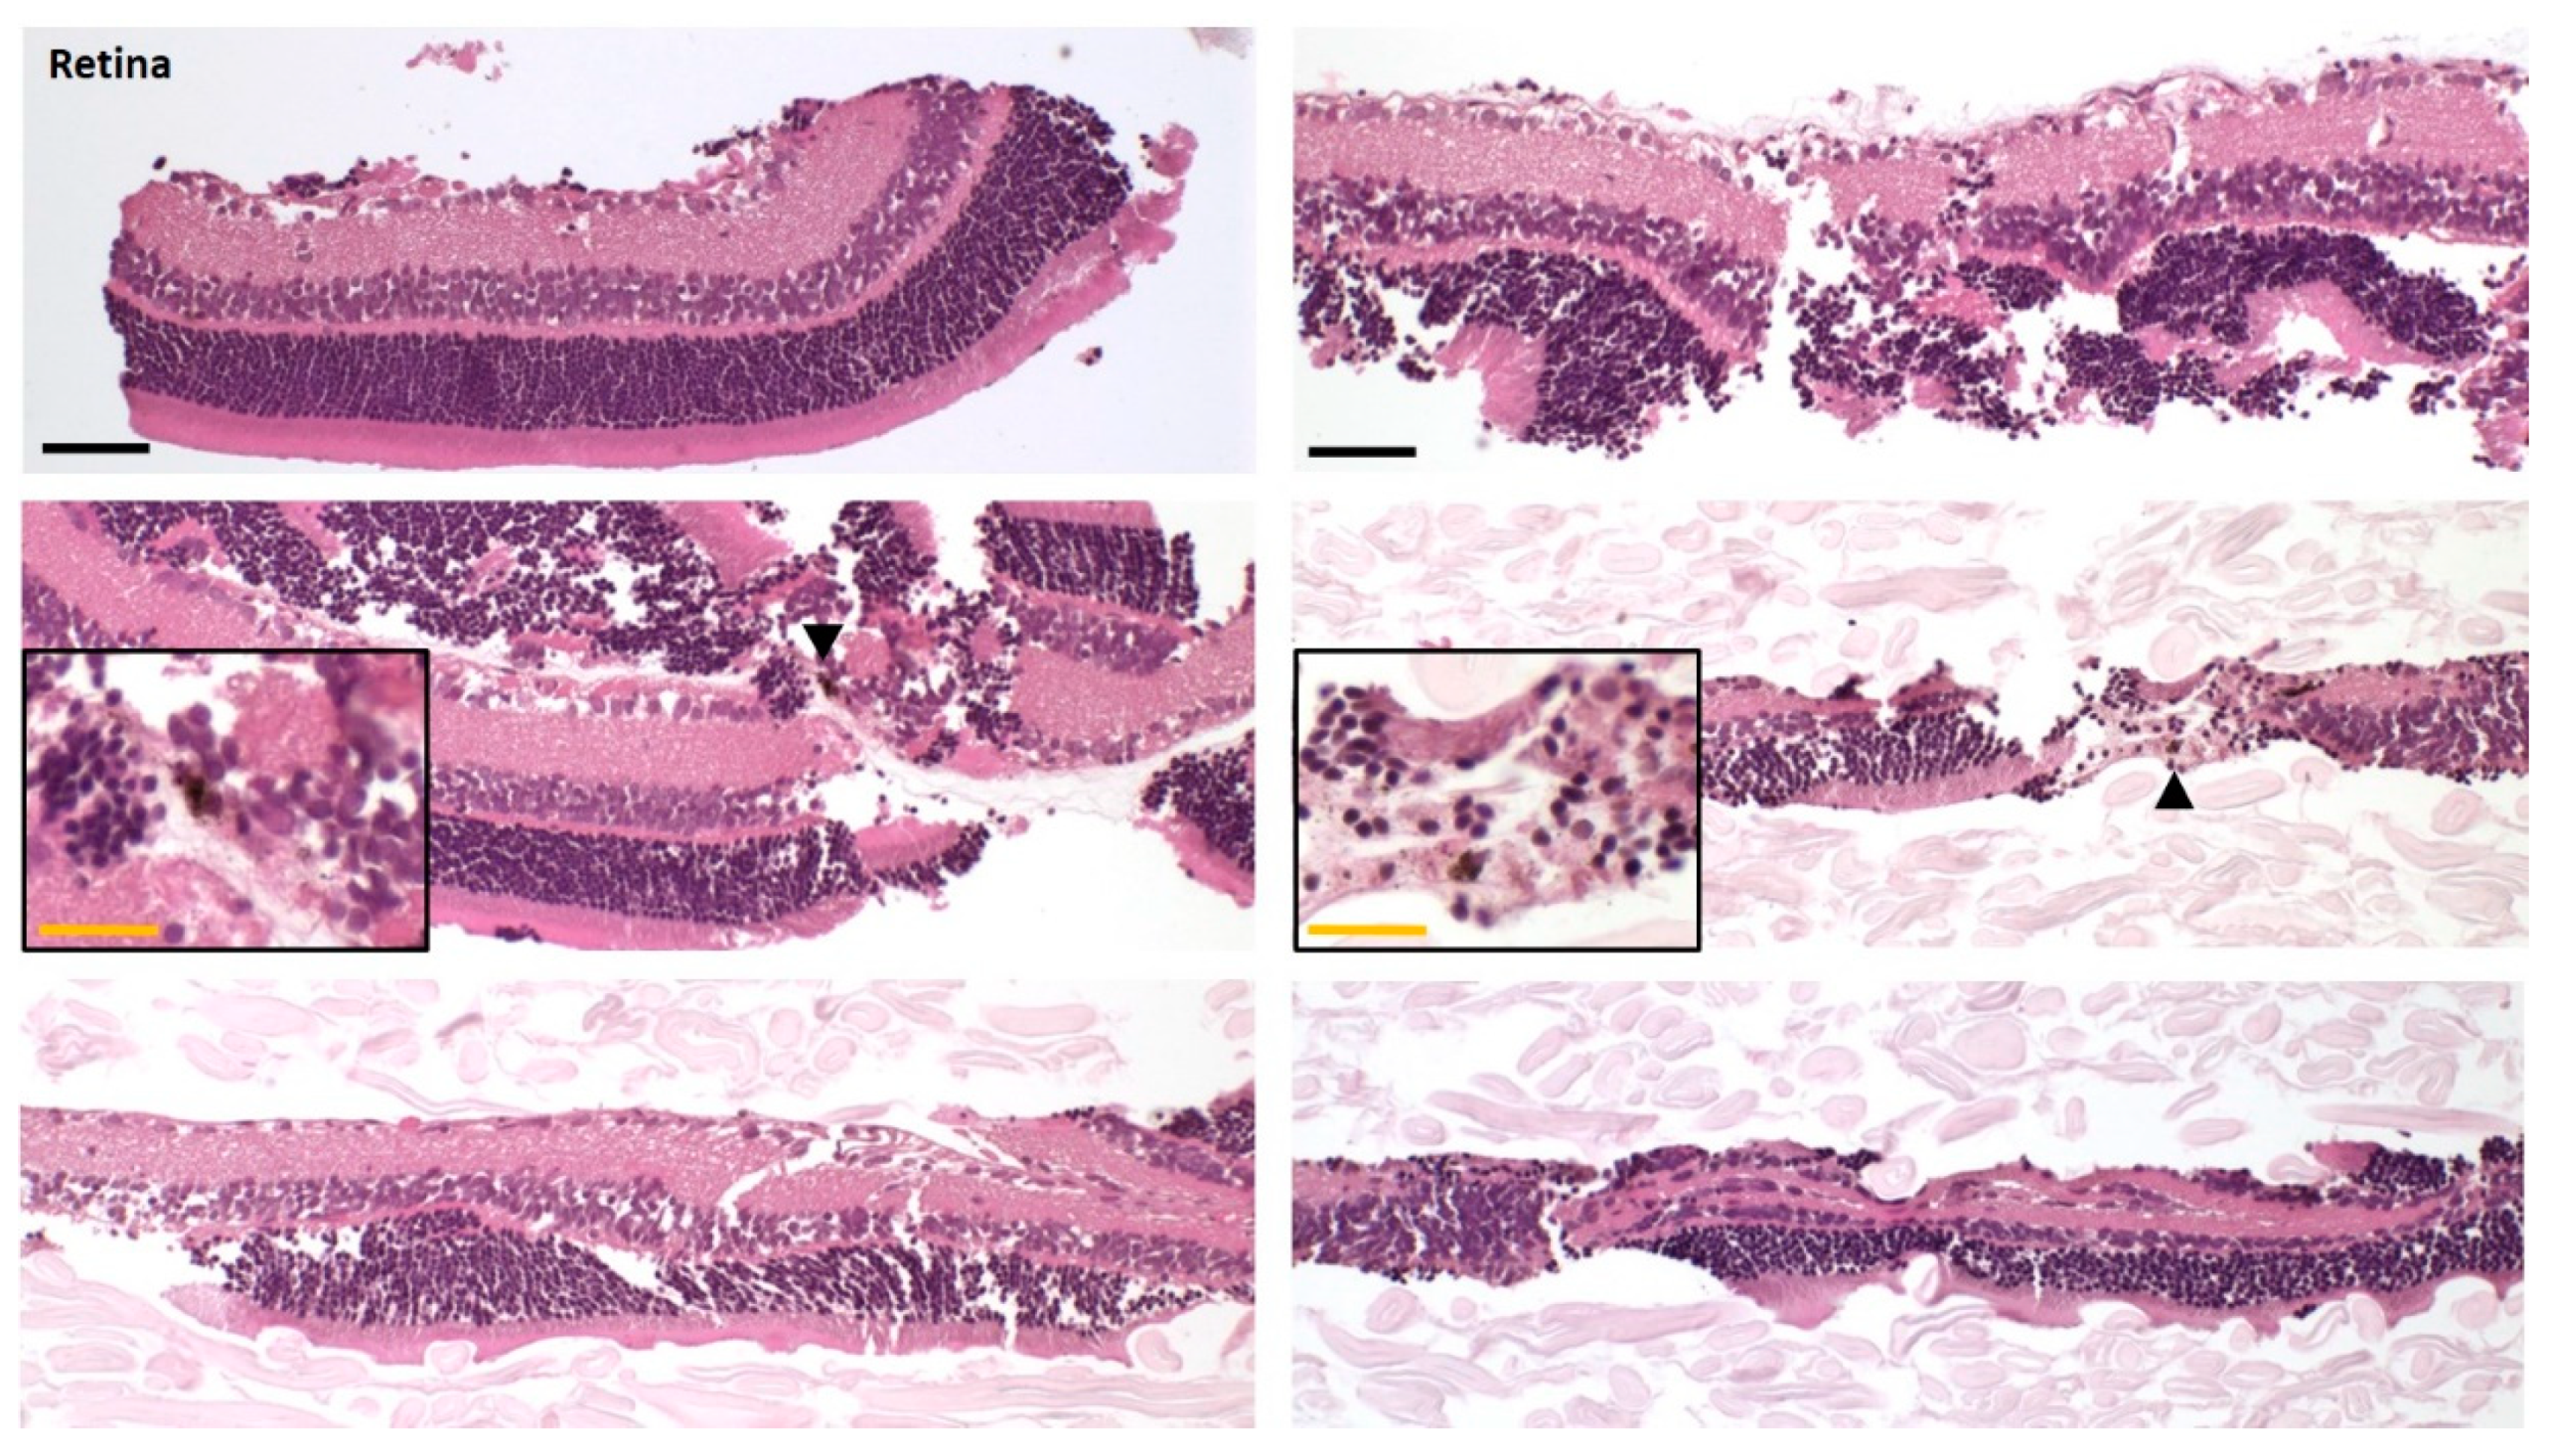

2.8. Histology

To investigate the level of cross-tissue contamination, we prepared the ocular tissues for histological examination using the above-described protocol. After separation of the different ocular layers, the tissues were cut into smaller pieces and transferred into histology cassettes. To avoid sample loss and to keep the samples flat, sponges and filter paper were used. The samples were fixed in 10% neutral buffered formalin for approximately 24 h, processed with an automated tissue processor (Tissue-Tek® VIP® 6, Sakura Finetek Europe B.V., Alphen aan den Rifn, the Netherlands), embedded in paraffin and cut in 3 µm sections. Staining with hematoxylin and eosin (HE) was performed according to standard protocols.

Small molecules exhibit high melanin binding potential, stressing the need for clean separation of the posterior segment tissues, retina and RPE-choroid, since a small contamination of the retina with melanin containing tissue could lead to a considerable over-estimation of retinal drug concentrations. Unfortunately, retina and RPE-choroid of the rat eye are very difficult to distinctly separate from one another. We chose to fix the eye in formalin before the separation process, as formalin is known to induce retinal detachment [

24] and preserve tissue structure. A short fixation time of 90 min, considerably shorter than the generally used tissue fixation times for histology purposes (overnight or longer), was optimal for our purpose.

Due to the massive concentration differences possible between pigmented and non-pigmented ocular tissues, we applied two methods to investigate retina contaminations with pigmented tissue. While the low melanin content determined in the pooled retinas via the less sensitive photometry was encouraging, the histology of the separated retinas demonstrated the efficiency of the separation process leading to essentially no contaminations with RPE-choroid. We consider this achievement of high importance for an accurate quantification of compounds with melanin binding potential in the retinal tissue.